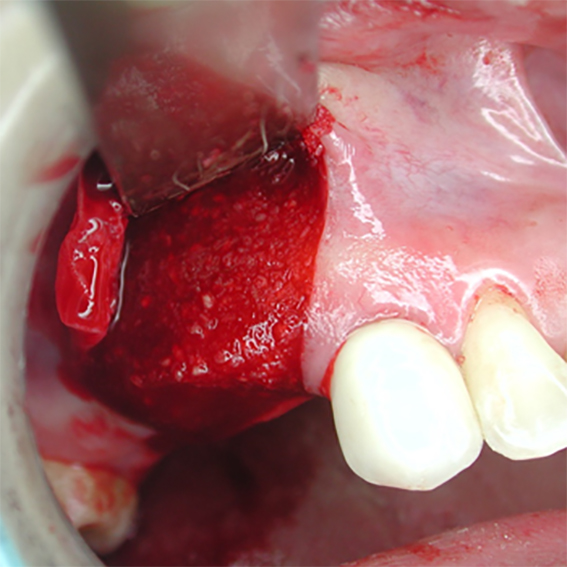

- A good dressing for raw bone surfaces

- Excellent would healing underneath

Pure titanium membrane of ultra-thin thickness of about 10 microns (0.01mm). Totally inert, biocompatible and non-biological thus removing the fear of disease transmission from collagen of bovine source. It allows ease of handling and adaptation over the operative site. Because of its mouldability, it does not require pin or screw fixation, thus avoiding the risks of pin or screw swallowing or aspiration. Excellent clinical performance in guided tissue regeneration. Resistance to infection after exposure. Primary wound closure is not necessary. No tissue reaction or wound infection.